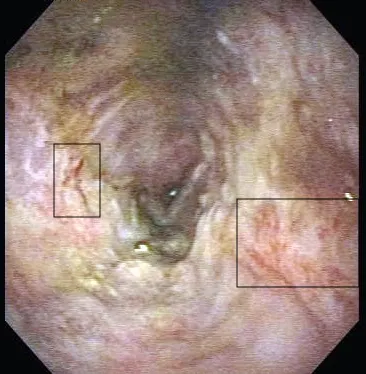

The chicken wing is removed endoscopically 24 hours after ingestion. Following foreign body removal, esophageal erythema and erosive lesions are noted (Figure 2). Moderate to severe esophagitis is also observed near the lower esophageal sphincter.

Endoscopic image of the esophagus following foreign body removal. The underlying esophagus has erosive lesions (boxes) and erythema. Moderate to severe esophagitis is observed near the lower esophageal sphincter.